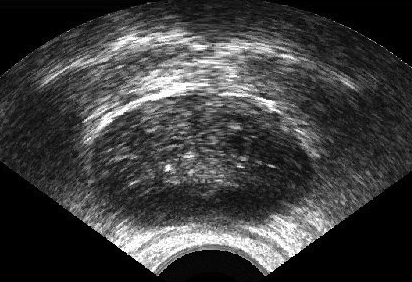

It is a challenge to validate any approach to segmentation. One has to measure the accuracy of the segment against ground-truth images. Ideally, if we have many users available to segment images, we can build “consensus segments”, or gold standard, to make more reliable measurements. Of course, this is usually not feasible with real images, for which there is no gold standard. Hence, we generated synthetic images whose gold segments were known a priori. For this reason, we used synthetic images that simulate transrectal ultrasound (TRUS).

TRUS images of prostates may be used to both diagnose and treat prostate diseases such as cancer. Starting with a set of prostate shapes , we created random segments through combinations of those priors, adding noise along with random translations and rotations, and we distorted the results with speckle noise and shadow patterns. Each image is thus created from its gold . Consequently, we can simulate user delineations by manipulating via scaling, rotation, and morphological changes, and we can simulate edits by running active contours with variable user-simulating parameters. The variability of user delineations was simulated according to several factors: error probability (), anatomical difficulty ( out of ), and the scaling factor for morphology (form to ). The user was modelled according to the level of experience (a random number from ), the user’s attention (a random number from ), and the user’s tendencies in terms of the segment size (a random number from ), whether tending to draw contours that are relatively small () or large ().

We generated 500 images from their corresponding gold-standard images111All images and their segments are available online: http://tizhoosh.uwaterloo.ca/. Furthermore, we generated 20 different segments for each image, assuming that there were 20 users. Figure 4 shows five examples of real and synthetic TRUS images. One should bear in mind that the purpose here was not to simulate the images realistically, but rather to have a base from which to generate variable segments from a perfect segment. Figure 5 shows an example of the gold segments and simulated user contours. The variability, coupled with the gold segment, is what is needed in our experiments.